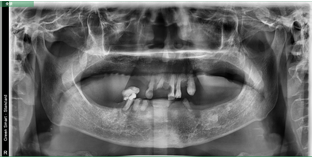

病歷一:

患者,女性,73歲。

主訴:多牙體缺失,余留牙體松動(dòng)不適,進(jìn)食效率低下(困難),要求治療。

治療方案:完善相關(guān)化驗(yàn)檢查,松動(dòng)牙拔除,并行全口種植桿卡修復(fù)治療。

術(shù)前片/術(shù)后片

選復(fù)合基臺(tái)(上頜)/選復(fù)合基臺(tái)(下)

桿卡試戴(上頜)/桿卡試戴(下頜)

咬合確定 /治療結(jié)束